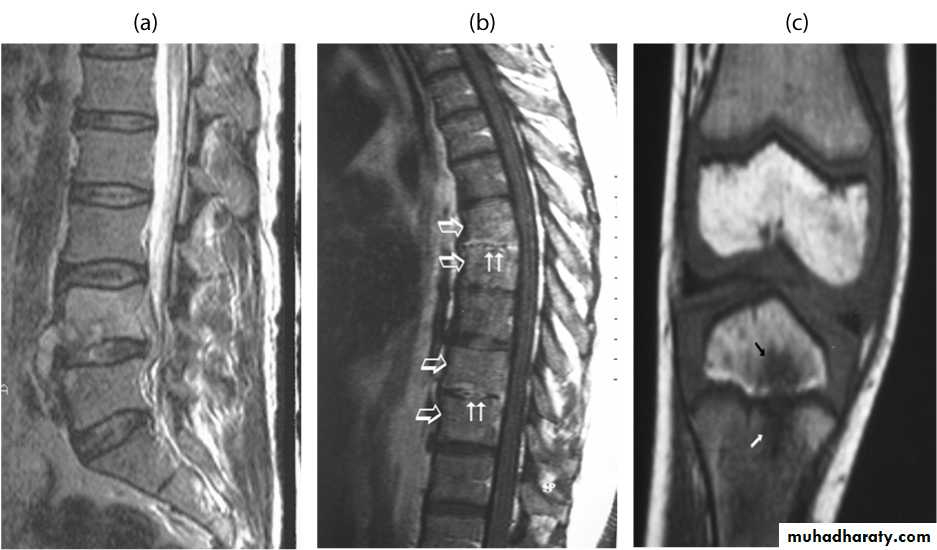

(A): MRI of lumbar spine in a patient with brucellosis showing evidence of paravertebral and epidural abscess (B): MRI of thoracic spine in a patient with brucellosis showing evidence of multifocal spondylodiskitis (C): MRI of tibia in a patient with brucellosis showing evidence of osteomyelitis.

Osteomyelitis of lumbar vertebrae